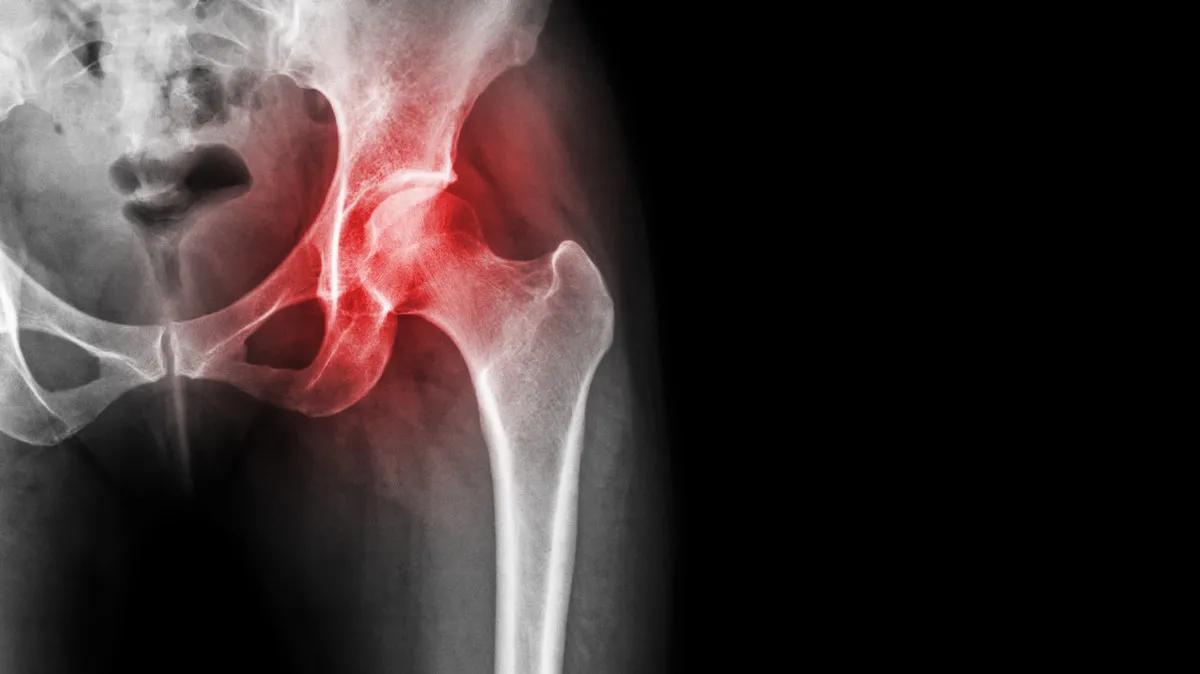

股骨头坏死是骨科常见疾病,发病的主要原因是股骨头供血不够,导致股骨头出现骨质疏松、病变,最终塌陷、坏死。

股骨头坏死的疼痛从哪来?

有人认为,疼痛是因为股骨头坏死引发了滑膜炎,关节腔里出现积液,造成了疼痛。

但这只是其中的一个原因,更主要的原因当股骨头供血不够,出现缺血坏死之后,股关节会承受的压力变得更大,而造成疼痛。

我们走路的时候,人体自身的重量会对股骨头造成挤压,力量从上往下传导的时候,在压力的作用下,它会产生微小的形变。

这时候如果关节软骨存在微骨折或者关节有炎症,使得关节腔有积液——要知道,关节里腔的积液没有办法往外排,这就导致了关节内部的压力会变大。

这时候当你站立或者行走,给股关节施加更大的压力时,高压就会刺激到神经感受器的末梢,产生疼痛的感觉。